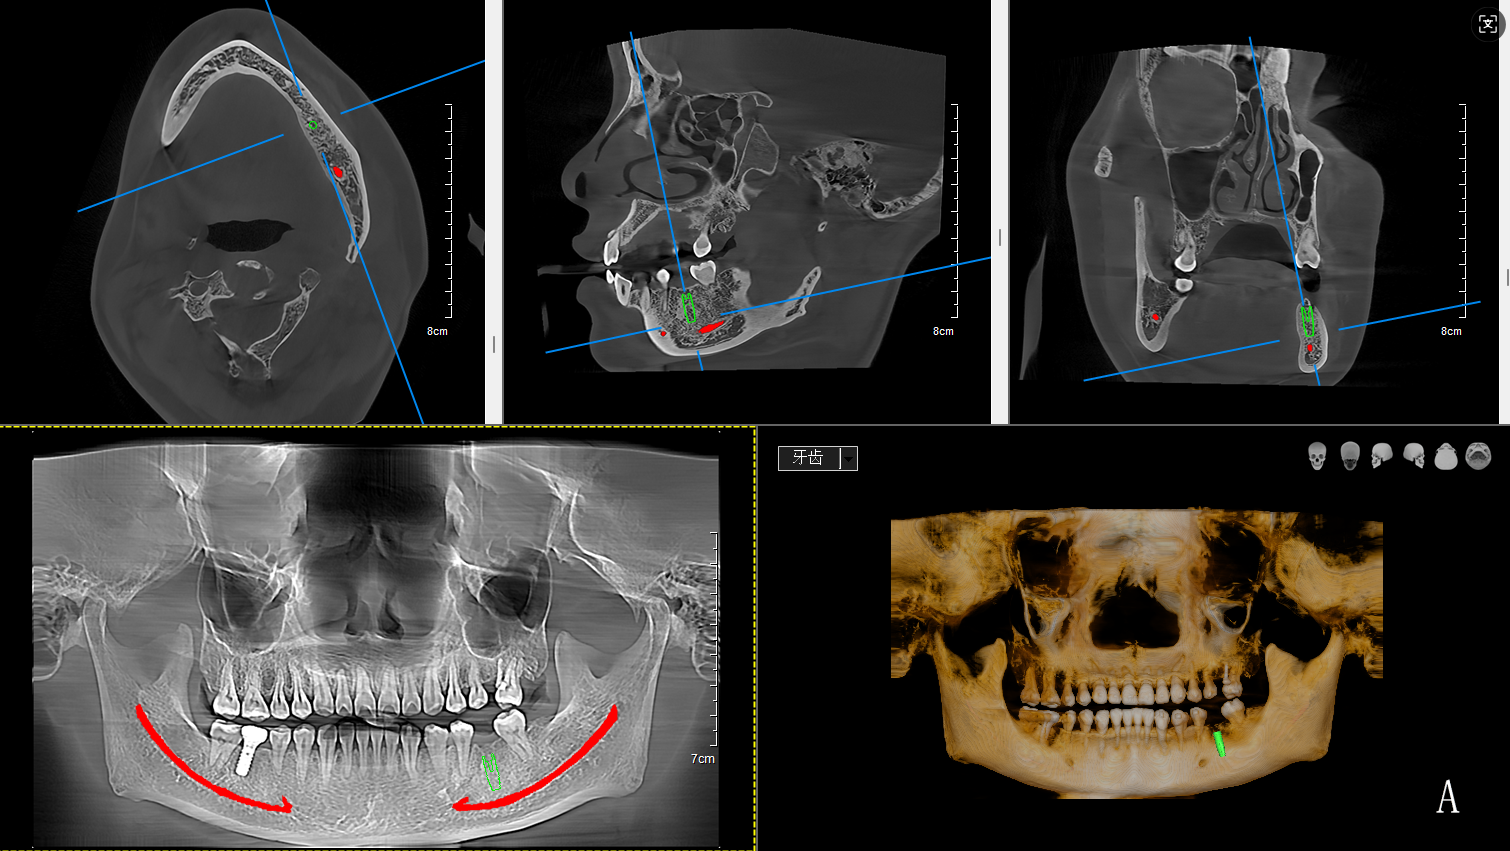

復(fù)雜牙齒矯正:對(duì)于埋伏阻生牙(如常見(jiàn)的阻生智齒)或多生牙病例,口腔CT能確定牙齒在頜骨內(nèi)精確位置、方向以及與鄰牙及神經(jīng)管的關(guān)系,避免拔牙時(shí)誤傷神經(jīng)或鄰牙牙根。

皓月CT自動(dòng)繪制神經(jīng)管、氣道分析